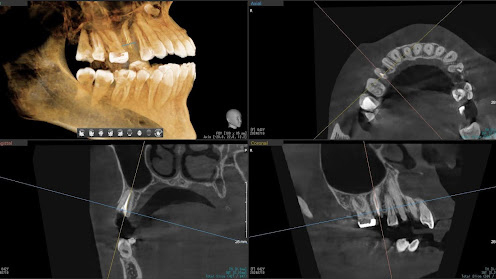

Before

枚方市のインプラントの症例

I・K 様 女性 40代

症状としては、左上5の歯根破折を起こしていたため、排膿と自発痛をみとめた。それにともなう骨の大きな欠損。

治療法としては、炎症が強くたったためと、炎症による頬側側歯肉の退縮を認めていたために、まず、抜歯を行い上顎洞内及び歯抜した周囲組織の回復を試みた。その後、患者様がインプラント治療を希望したため、薄い上顎骨に対しては、グラフトレスサイナスリフト、骨欠損部には、人口骨補填を行い、頬側歯肉が退縮していることを改善するために、1回法でリーリングアバットメントを装着して、アバットメントの上に歯肉が覆うようにして、歯肉のボリューム回復を行った。2か月後、インプラントが骨と結合していることを確認して、光学印象を行い、2週間後にアバットメントとジルコニアクラウンを装着した。

治療結果としては、大幅な骨欠損があったが、グラフトレスサイナスリフトと骨欠損部に人工骨を補填して、抜歯した穴が自然に治る状態にしたことで、2か月半という短い期間での治療を完了することができた。(仮に、GBRや通常のサイナスリフトでの治療を行っていたら、最低でも1年は、かかってくる治療であると考える。)また、今回は、即時荷重を避け、1回法での治療を行ったことで、噛めない期間ができてしまったが、1回法で行ったことにより、歯肉のボリュームが増して、ブラッシングがしやすい口腔内環境にすることができた。低侵襲で、短時間で、治療を終えることができ、また、審美性・機能性の回復も行えたことができた。

治療の期間・回数:約2.5か月、6回

治療の価格:368,500円(税込)

治療費の内訳:インプラント基本料(フィックスチャー及び手術費用、投薬費用、レントゲン費用、インプラント上部費用(アバットメントおよびジルコニアクラウンの費用用)330000円(税込み)。オプション費用グラフトレスサイナスリフト費用プラス人工骨費用 38500円(税込み

治療のリスクや副作用:手術後に、痛みや腫れ、出血、合併症などを引き起こす可能性があります。噛む感覚がご自身の歯と異なる場合があります。見た目がご自身の歯と異なる場合があります。手術後にメインテナンスを継続しないと、インプラントが抜け落ちる可能性があります。